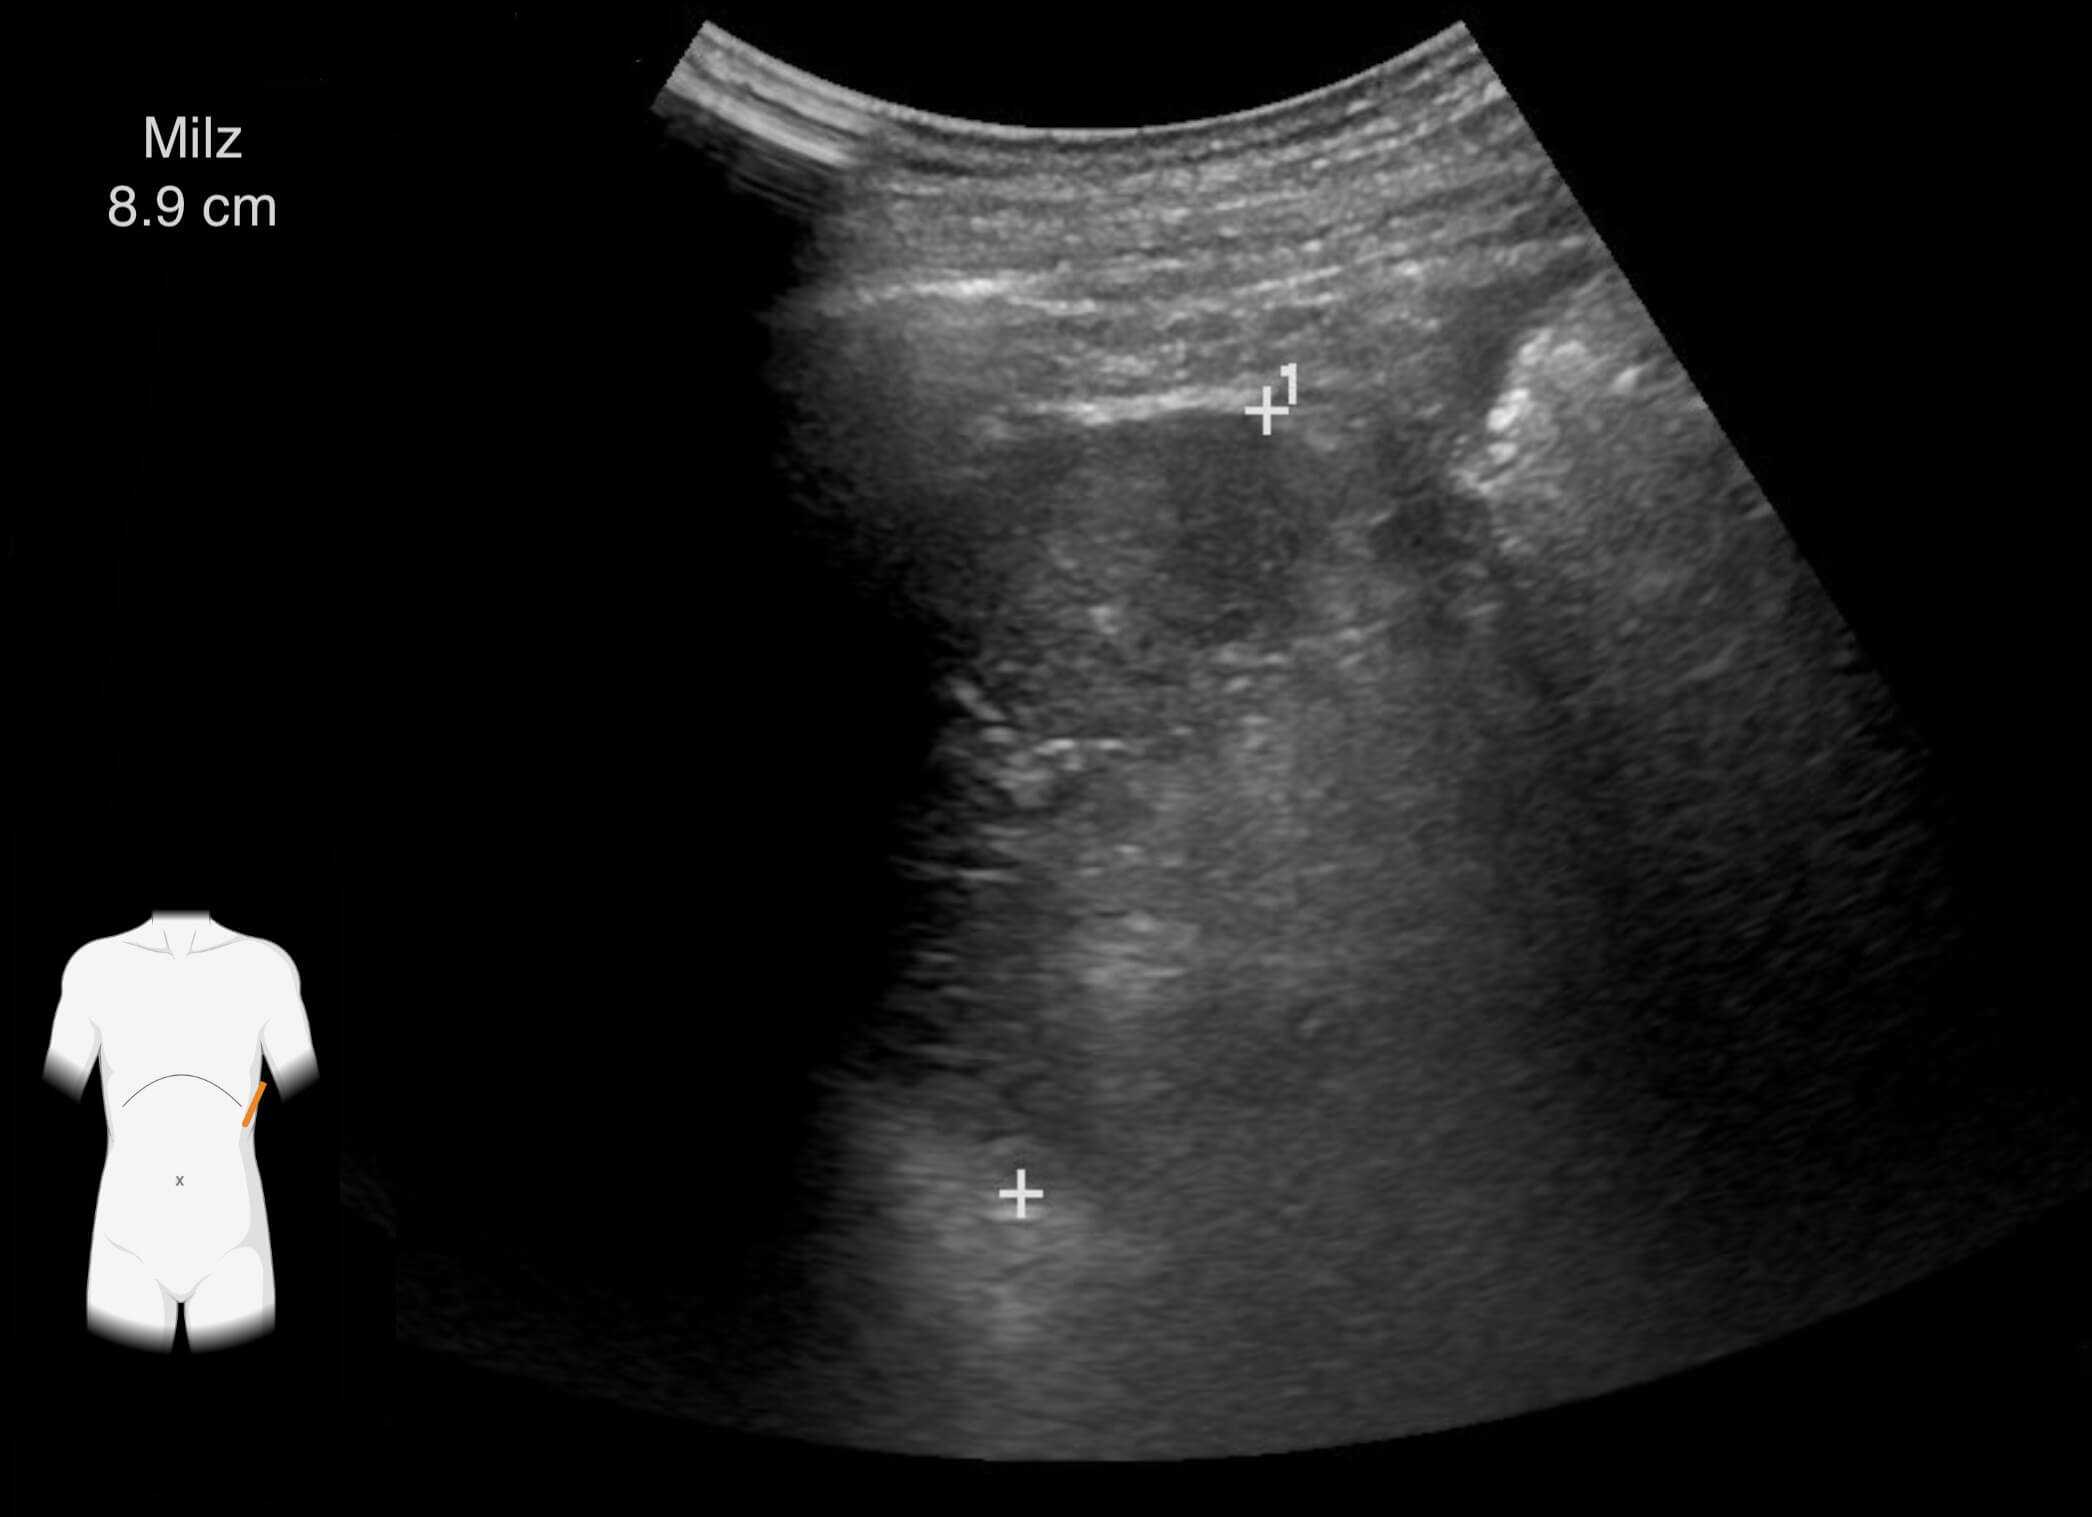

Die Ergebnisse der durchgeführten Untersuchungen kannst du dir hier anschauen:

Die Befunde geben eindeutige Hinweise auf die Erkrankung von Frau Lorenz. Wie bewertest du die Ergebnisse?